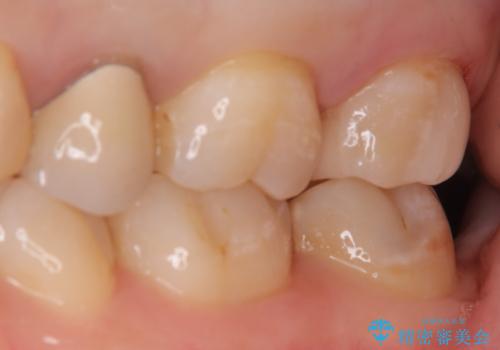

- 定期検診にて虫歯が見つかった患者様です。

金属のインレーの下と、歯と歯の間も虫歯だったため、つなげた形でセラミックインレーにて修復を行なっています。

e-max プレスインレーを用いることで、適合の良い治療ができます。